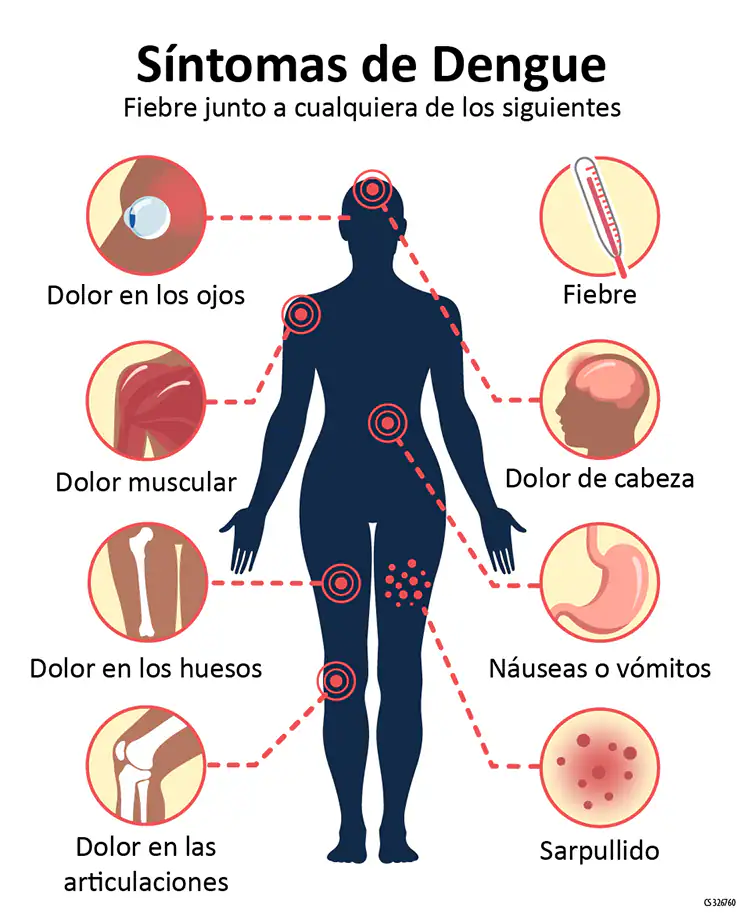

Adquiere este nombre porque los síntomas son algo diferentes de los de la neumonía común: los casos suelen empezar con dolor de cabeza y fiebre, y luego aparece dolor de garganta, tos seca, dolores musculares, de articulaciones y de rodilla y cadera, sarpullido rojo, vómitos y diarrea. Se da en niños desde los cinco años hasta la edad adulta.